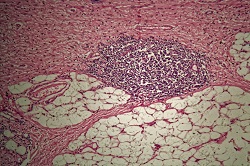

EU-funded scientists working on the HELICOMARK project have found ways to assess stomach cancer risk in blood samples using the body’s immune response as a tool. Around 700 000 people die each year around the world from stomach cancer, the third most common cause of cancer death. Together Japan, Korea and China account for almost 70 % of all cases but it is also common in Latin America and Eastern Europe, and patients generally have a poor survival prognosis. A major cause of stomach cancer is the Helicobacter pylori germ. “H. pylori as a bacterium is very genetically variable and the variation more or less follows ethnicity, with East Asian versions of H. pylori being more carcinogenic,” says project coordinator Professor Samuel Lundin, a professor in the department of Microbiology and Immunology at the University of Gothenburg, Sweden. “We have been analysing in very high detail the antibody responses to H. pylori to pinpoint the more risky H. pylori bacteria present in blood samples, and analysing how this is associated with stomach cancer risk.” Peptide arrays Researchers produce peptide arrays to profile a patient’s immune response to H. pylori by synthesising peptides on a glass chip. “Technologies are available that allow us to add one amino acid letting it react, then washing it away and adding another amino acid till a peptide sequence is produced on the glass chip,” Prof Lundin explains. Serum samples from Nicaragua, where there is a high risk of stomach cancer, and Sweden, were added to the 200 000 peptides on the chip. “Depending on the antibodies produced, some of them will bind to some of the peptides. Then you add another antibody that is fluorescently labelled so you light up those peptides,” Prof Lundin says. “The assay shows the existence of these antibodies, so what we are doing is mapping the antibodies by using the peptide chip,” he explains. “From this we get a score of how well the antibodies have bound to peptides, and to which of the 200 000 peptides.” This produces a specific ‘fingerprint’ for each person which can then be compared with those who developed the cancer. Mapping proteins “We mapped all the proteins that will elicit an antibody response if you have H. pylori, and all the epitopes of those proteins (the parts of the proteins to which antibodies bind),” says Professor Lundin. “We have shown that only two or three of those epitopes are diagnostic in patients, the others produce antibodies even if the patient doesn’t have H. pylori.” This method of mapping the epitopes has been patented. “We identified the peptides, where, if the patient has antibodies to them, we know there is a high risk of developing stomach cancer,” Professor Lundin explains. The key to the project’s success was access to blood samples as well as biopsies from the same person. “We can culture the bacteria from the biopsies and analyse the person’s H. pylori strains using genomic analysis,” he continues. The same person’s antibody response is analysed to see the peptide sequences they respond to. “It’s uncommon to have all of this information together and that was crucial for us.” Professor Lundin received a three-year Marie Curie grant that funded two years in Perth, Australia, working with Nobel Laureate Barry Marshall, one of the two scientists who discovered H. pylori.